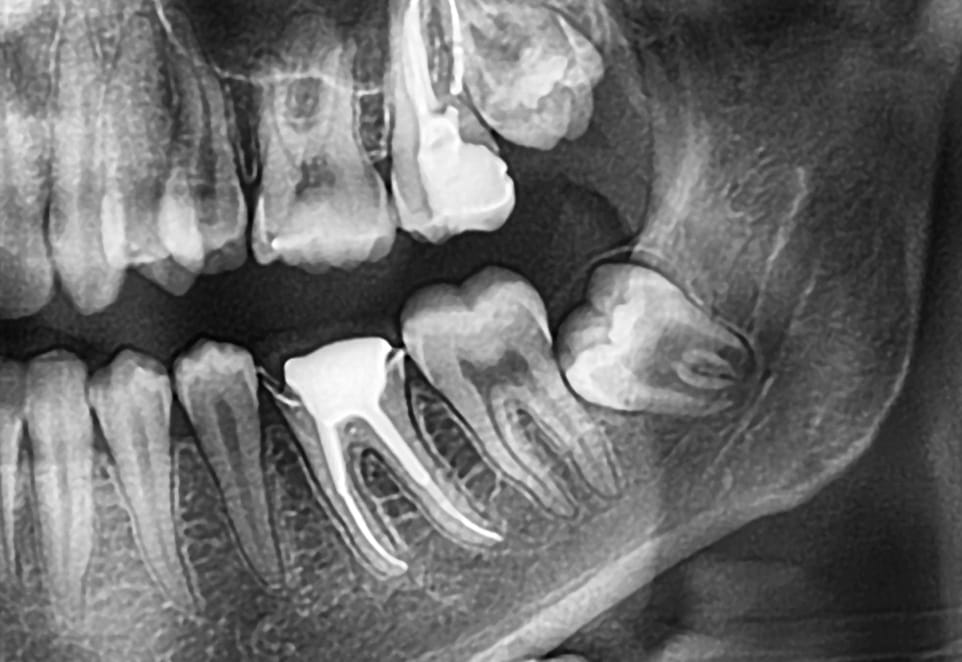

Gömülü diş, normal şartlarda ağız içine sürmesi gereken ancak çene kemiği ya da diş eti dokusu altında kalarak sürme sürecini tamamlayamayan diştir. En sık karşılaşılan gömülü dişler 20 yaş dişleridir. Bu dişler çoğunlukla çenede yeterli alan bulunmaması nedeniyle ağız içine çıkamaz; bazı durumlarda tamamen kemik içinde kalırken, bazı durumlarda ise kısmen sürmüş şekilde konumlanabilir.

Çekim süreci detaylı bir muayene ile başlar. Röntgenler yardımıyla dişin çene kemiği içindeki konumu, sinirlerle olan mesafesi ve çevre dokularla ilişkisi değerlendirilir. Bu aşama, yapılacak işlemin sınırlarını belirleyen en kritik adımdır. Doğru planlama, hem işlemin süresini kısaltır hem de iyileşme sürecini olumlu etkiler.

Ana sinire yakın konumlanmış gömülü dişlerin çekimi, diğer gömülü dişlere kıyasla daha fazla dikkat ve planlama gerektirir. Alt çenede bulunan ve dudak, çene ile dişlerin hissini sağlayan ana sinir (inferior alveolar sinir), bazı gömülü 20 yaş dişlerine oldukça yakın seyredebilir. Bu durum, çekim sırasında sinirin etkilenme riskini gündeme getirse de, doğru değerlendirme ve uzman yaklaşımı ile bu risk büyük ölçüde kontrol altına alınabilir.

Çekim öncesinde alınan detaylı röntgenler ve gerekirse üç boyutlu görüntüleme yöntemleri sayesinde diş ile sinir arasındaki mesafe net olarak belirlenir. Sinire çok yakın vakalarda, dişin tamamının çıkarılması yerine yalnızca sorunlu kısmının alınması gibi alternatif yöntemler tercih edilebilir. Deneyimli bir ağız, çene ve diş cerrahı tarafından yapılan işlemlerde kalıcı sinir hasarı riski oldukça düşüktür. Bu nedenle ana sinire yakın gömülü diş risklidir demek yerine, “özel planlama gerektirir” demek daha doğru bir yaklaşım olacaktır.